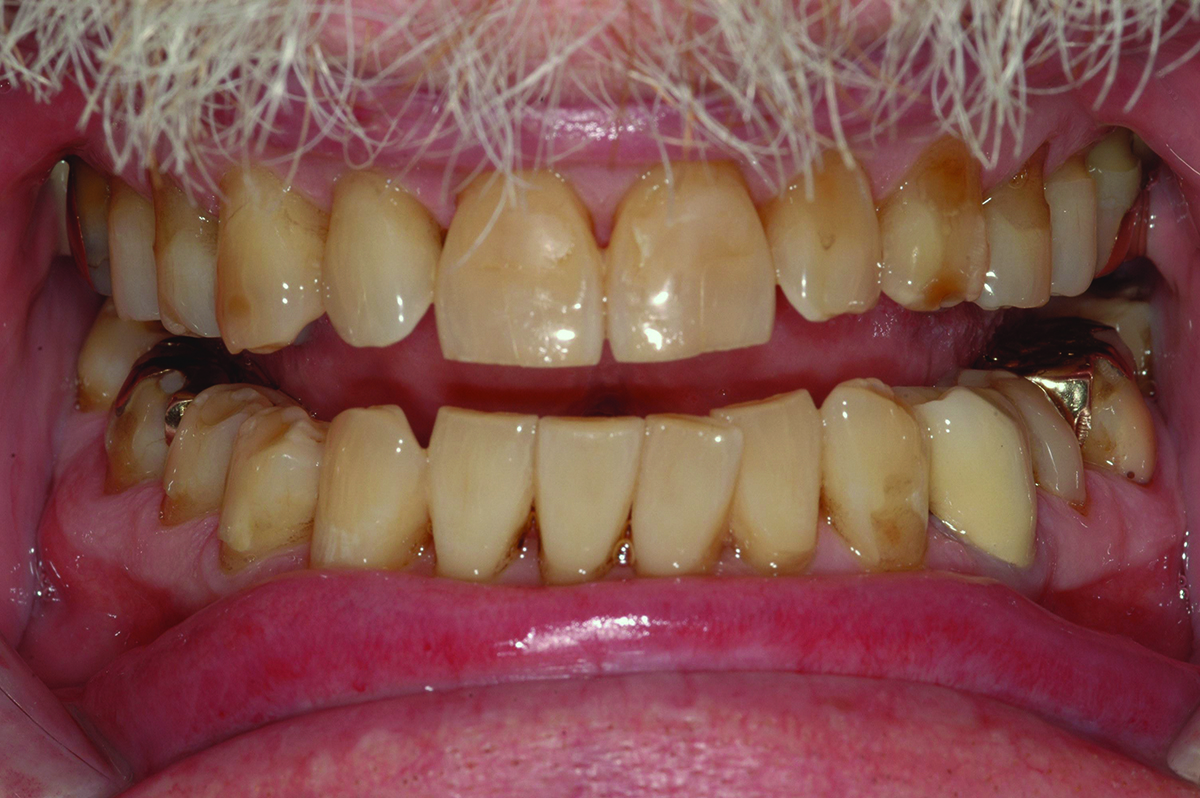

Close-up view of patient’s dentition in 2009.

Figure 1

Close-up view of patient’s dentition in 2017 showing increased facial and buccal erosion over the past 8 years.

Figure 2

Biomechanical: Significant tooth structure loss had occurred between 2009 and 2017 (Figure 1 through Figure 3). Severe attrition had occurred on the anterior teeth, especially tooth No. 11. Severe erosion and abrasion were present on teeth Nos. 11, 18, 20, 21, 28, 29, 31, and 32 (Fig-

Extreme changes in an adult dentition can occur rapidly when multiple risk factors are combined. In the case presented, the male patient’s dentition changed dramatically over an 8-year period due in large part to gastroesophageal reflux disease (GERD) and daytime clenching. Significant generalized enamel and dentin loss had occurred, and the patient’s maxillary lateral teeth had shifted despite a healthy periodontium.